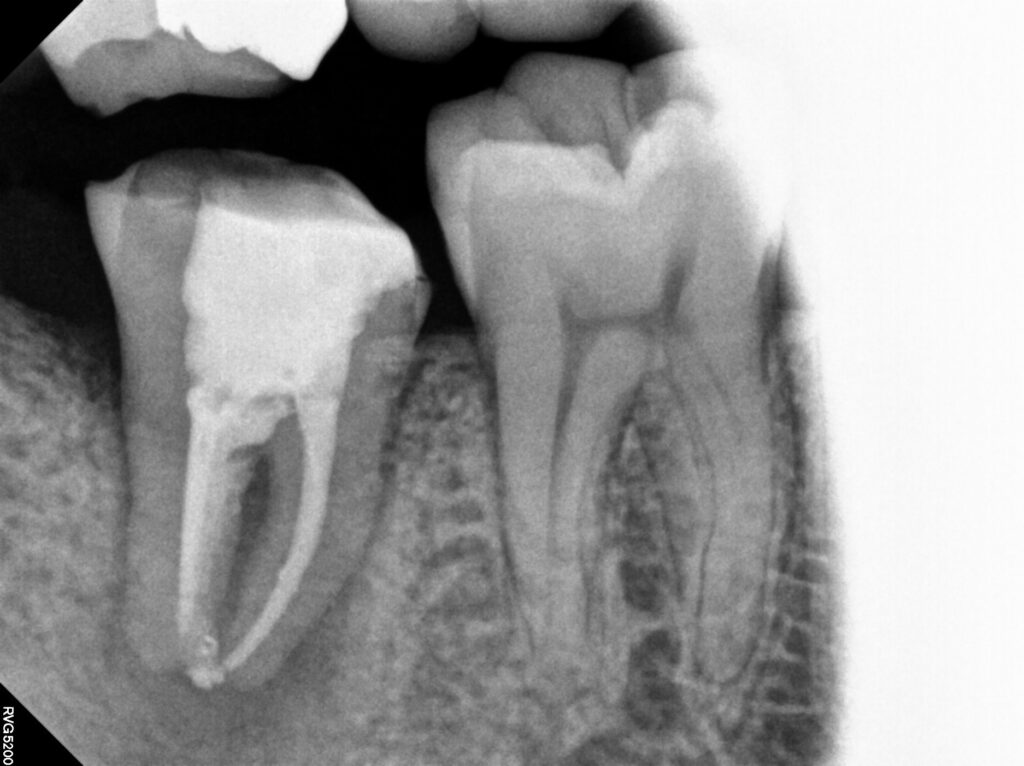

근관 내 ledge(근관을 확대하거나 기구를 삽입하는

과정에서 원래의 경로를 벗어나 더이상 진행되지 않게

막는 인공적인 턱이 생긴 상태)가 형성되어

치근단 접근이 어려웠지만 초음파를 이용한

근관 세척법을 통해 최대한 세척해내주었습니다.

더불어 c형 근관을 가지고 있어 분리되지 않고

하나로 이어져 내부 구조가 매우 복잡하고

불규칙하였는데요.